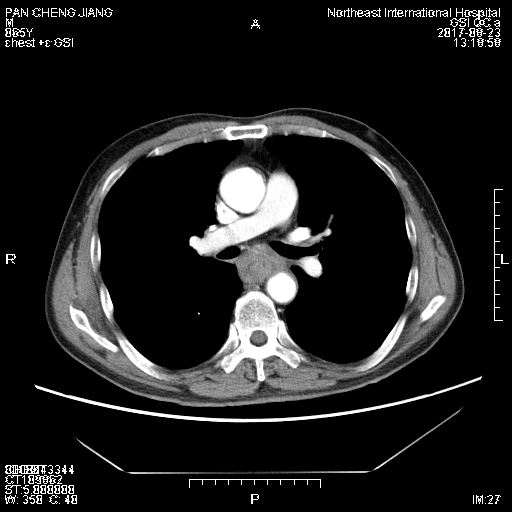

2017年6月潘老先生因进食出现哽咽进行胃镜检查确诊为食道鳞癌。以前身体一向健康的潘老先生一家得知这一消息后万分着急。其女儿一心想要为老父亲治好病,经过辗转打听,来到东北国际医院。在放疗科门诊,为进行更准确的分期,金主任为患者进行胸部增强CT检查,检查结果发现食管中段病变部分与左主支气管起始部后壁分界不清,左主支气管起始部后壁局部毛糙,连续性未见中断。并且经外科评估暂无手术指征,经过多学科会诊,制定治疗方案为先行新辅助放疗。同年8月,潘老先生开始接受放疗,放疗后1个月再次复查胸部增强CT:气管隆突与病变处可见脂肪间隙,左主支气管结构清晰完整,未见浸润生长。经外科再次评估,于2017年11月03日行食管癌根治性手术,术后患者恢复良好。如今潘老先生又恢复到正常生活。

放疗前

放疗后